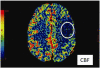

Quantitative imaging (QI) is increasingly applied in modern radiology practice, assisting in the clinical assessment of many patients and providing a source of biomarkers for a spectrum of diseases. QI is commonly used to inform patient diagnosis or prognosis, determine the choice of therapy, or monitor therapy response. Because most radiologists will likely implement some QI tools to meet the patient care needs of their referring clinicians, it is important for all radiologists to become familiar with the strengths and limitations of QI. The Association of University Radiologists Radiology Research Alliance Quantitative Imaging Task Force has explored the clinical application of QI and summarizes its work in this review. We provide an overview of the clinical use of QI by discussing QI tools that are currently used in clinical practice, clinical applications of these tools, approaches to reporting of QI, and challenges to implementing QI. It is hoped that these insights will help radiologists recognize the tangible benefits of QI to their patients, their referring clinicians, and their own radiology practice.